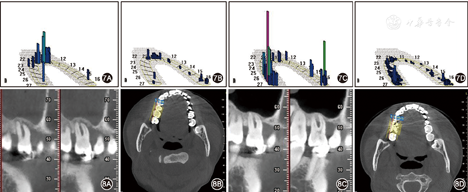

注:-为Ⅰ度松动;=为Ⅱ度松动;+为Ⅲ度松动

注:LTA为左侧颞肌;RTA为右侧颞肌;LMM为左侧咬肌;RMM为右侧咬肌;LCG为左侧颈群肌;RCG为右侧颈群肌;LDA为左侧二腹肌前腹;RDA为右侧二腹肌前腹

前后

力评估分析系统检查结果 A:调

前,前伸运动时存在干扰;B:调

后前伸运动干扰消除;C:调

前侧方运动时左侧存在干扰;D:调

后侧方运动时左侧干扰消失

后侧方运动时左侧干扰消失患者女性,18岁,于2011年11月就诊于武汉大学口腔医学院牙周科。就诊4年前发现牙齿松动,出现缝隙并逐渐增大。曾于外院行洁治治疗无明显效果。否认家族史。

口外检查可见面部不对称和张口偏斜。口内检查可见牙龈红肿,前牙区和后牙区均存在牙齿移位和明显的牙间隙(图1)。牙周检查结果见图4A,探诊出血阳性位点达100%,探诊深度超过4 mm的位点达65%,松动牙占全口牙85%,其中Ⅲ度松动的牙齿数量达50%。影像学检查结果显示除外个别牙,余牙的牙槽骨吸收均达根长的1/3至根尖,同时发现存在右侧上颌窦炎(图5A)。应用K7咬合评估分析系统(K7 evaluation system,Myotronics-Noromed Inc,美国)检测发现患者双侧咀嚼肌电位严重不对称,下颌运动向左偏斜达17.3 mm(图6)。咬合力评估分析系统(T-scan system,Tekscan Inc,美国)显示存在早接触和

干扰(图7)。

初始治疗持续3个月,通过口腔卫生指导,洁治刮治及联合使用盐酸米诺环素控制牙周炎症。评估结果显示,探诊出血阳性位点百分比下降至27%;并发现随着肿胀牙龈逐渐恢复健康,13和14间缝隙逐渐关闭。2012年12月针对患者的咬合问题进行咬合干预治疗,包括咀嚼肌经皮电刺激治疗和调

。经皮电刺激治疗后,患者即刻感觉舒适,双侧咀嚼肌电位趋于平衡。同时,检查发现张口时下颌偏斜得到纠正(图6)。随后行调

治疗消除咬合创伤(图7)。治疗后每3~6个月进行定期维护治疗。

3年后随访显示,牙龈轻度红肿,病理性移位的25自动排齐,21和22以及23和24间缝隙关闭(图2)。探诊深度超过4 mm的位点百分比降至14%,Ⅲ度松动的牙齿仅占11%。影像学检查结果示牙槽骨骨量和密度均有增加,可见26、27、36近中和15、16的骨量明显增加;右侧上颌窦的炎症也得到控制(图5B)。图8示CT影像是在同一断层获取,15、16的放大影像清楚可见明显的骨量增加。8年后随访结果显示,病理性移位的牙齿未复发(图3),牙龈炎症控制良好,牙松动情况持续减轻。从2011年初始治疗至2019年,8年多来患者的牙周及整体情况显著好转;复查结果显示牙龈无明显红肿,回位牙齿维持稳定并未复发。无探诊深度超过4 mm的位点,Ⅱ度及以下松动牙齿仅占8%,无Ⅲ度松动牙齿(图4B),除15、16牙龈明显退缩,涉及退缩的还有36和24、25、26、27。影像学检查结果显示牙槽骨骨量和骨密度均进一步增加,骨白线逐渐清晰(图5C,图8)。患者对治疗结果非常满意。